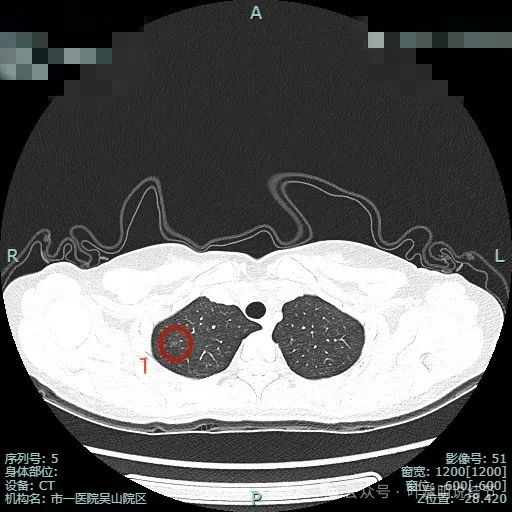

病灶1:右上叶淡磨玻璃结节,整体轮廓较清,考虑肺泡上皮增生或不典型增生可能。